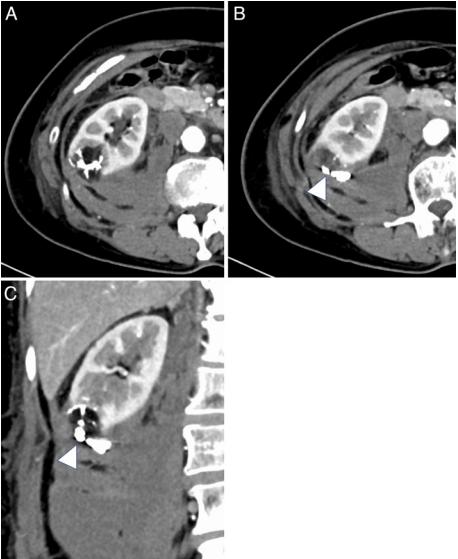

4-F血管造影导管(RC-09;Medikit, Tokyo, Japan)经右股动脉插入右肾动脉。血管造影显示,在弯曲的母血管周围有一个微动脉瘤,有大量造影剂外渗(图3A)。1.9-F的微导管通过0.014英寸的微导丝尽可能地进入母动脉(图3B)。NBCA和乙二磺酸油以1:2的比例混合,(33% NBCA),缓慢持续注射,填充微动脉瘤及近端动脉分支的出血点。(图3C)。术后血管造影未见造影剂外渗(图3D)。随访CT证实血肿缩小,出血部位充满NBCA碘化油铸型(图4)。随后的血液检查未发现贫血进展或肾功能恶化。患者于TAE术后14天无并发症出院。

图4、经导管动脉栓塞后10天的增强ct显示出血部位充满了n -氰基丙烯酸丁酯-脂醇铸型(箭头),显示血肿缩小